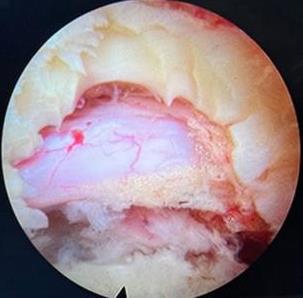

摘要:目的 比较内镜射频消融术(RFA)与光动力疗法(PDT)联合胆道支架置入治疗不可切除肝外胆管癌的远期疗效。方法 回顾性分析2018年2月-2023年2月于该院接受内镜RFA或PDT治疗的胆管癌患者的临床资料,根据手术方法不同,将患者分为RFA组(n = 32,行内镜RFA联合胆道支架置入)和PDT组(n = 21,行内镜PDT联合胆道支架置入)。比较两组患者治疗次数、支架通畅期、总体生存期和并发症发生率,并分析影响患者生存期的危险因素。结果 RFA组与PDT组总体生存期分别为14.0(95%CI:11.8~16.2)和18.0(95%CI:15.4~20.6)个月,支架中位通畅期分别为4.0(95%CI:2.7~5.3)和3.5(95%CI:2.3~4.7)个月,差异均无统计学意义(P > 0.05);多因素Cox回归分析显示,内镜下RFA或PDT治疗次数的HR^ = 2.417,≥ 2次是影响总体生存期的保护性因素(P = 0.018),而TNM分期的HR^ = 0.300,Ⅲ期至Ⅳ期是影响总体生存期的危险性因素(P = 0.002);两组患者临床成功率均为100.00%;两组患者并发症总发生率[28.13%(9/32)和23.81%(5/21)]比较,差异无统计学意义(P > 0.05)。结论 内镜RFA与PDT联合胆道支架置入,治疗不可切除肝外胆管癌的远期疗效相似。内镜RFA或PDT序贯治疗 ≥ 2次,能够有效地延长患者的总体生存期。